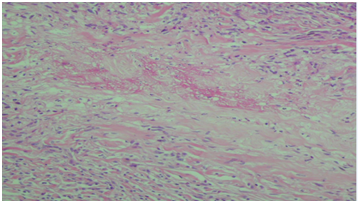

With a closer view is possible to see the degenerated collagen being discharged outside through the hair folllicle (Figure 2) and in the dermis, palisaded granulomas with necrobiotic collagen (Figure 3). This finding aims to a perforating dermatosis. There are not mucin deposits with Alcian blue staining. Neither is it present elastic fibers with the staining for their recognition.

Figure 3 Palisaded dermal granulomas and necrobiotic collagen in the center (HE 10 X).